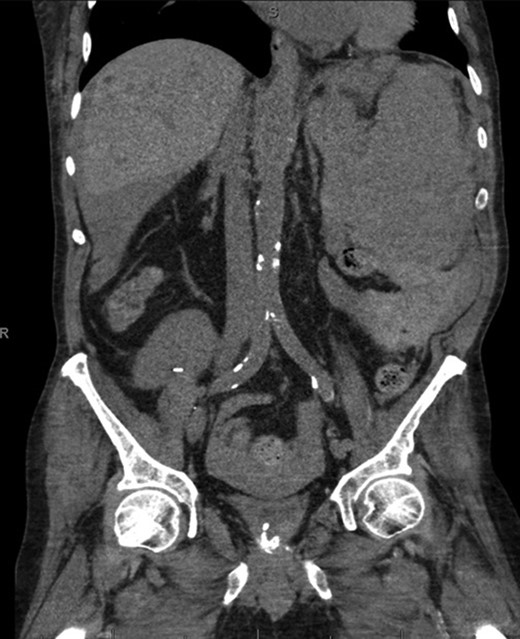

Coronal CT imaging demonstrating splenomegaly with splenic capsule rupture at the inferior pole with heterogeneous fluid in the paracolic gutters and perisplenic region suggestive of hemoperitoneum.